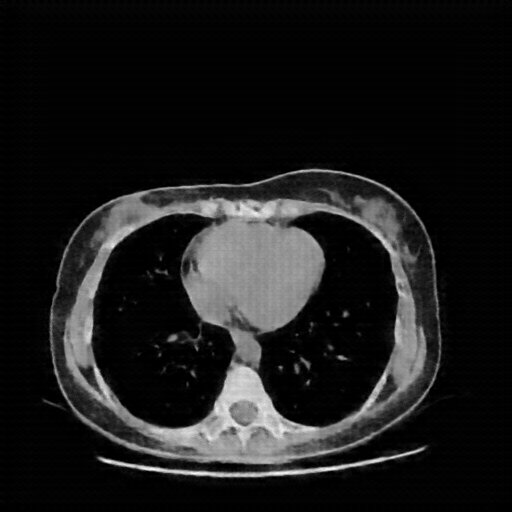

Original VENOUS CT scan

Full window (WL 1023.5, WW 4095 β†’ Low βˆ’1024, High +3071)

Actual HU range: [-160.0, 240.0]